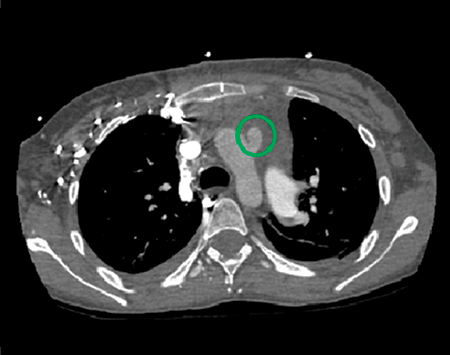

Postoperative mediastinal window showing the location of the modified Potts shunt (green circle).

As the patient was not a candidate for lung transplantation, the decision was made to perform a palliative unidirectional valved Potts shunt – a connection between the main pulmonary artery and the descending aorta – with simultaneous closure of the atrial septostomy. This would effectively generate Eisenmenger’s physiology with a “pop-off” valve from the pulmonary to the systemic circulation, providing right ventricular afterload reduction while maintaining cardiac output and preserving upper body oxygenation. A CT examination of the chest confirmed Potts shunt patency. She was discharged home on postoperative day 21 to take intravenous epoprostenol, ambrisentan, sildenafil, and furosemide. She was anticoagulated with warfarin and aspirin.